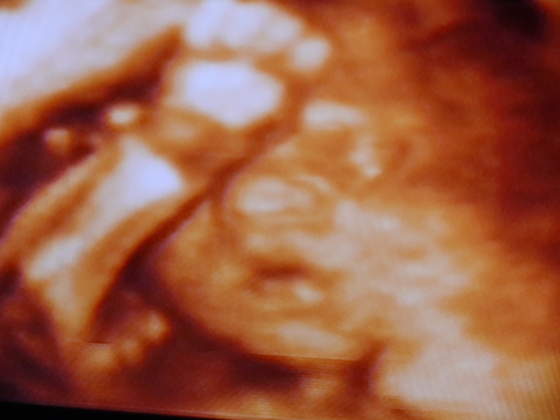

meczy mnie ta koncowka, brak snu, bole miesni i inne dolegliwosci, zreszta same wiecie. Jeszcze troszke i bede tulic swoja corcie:-):-):-)